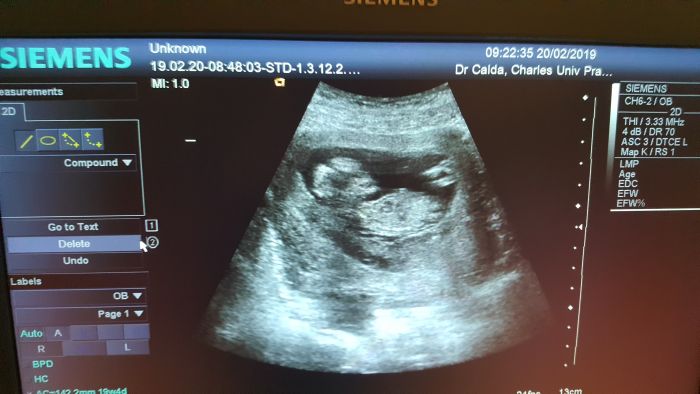

Autor: Moxha 20.2.2019 v 13:49

Ahoj holky.Tak dnešní kontrola v 13 týdnu a vše ok.Zítra mě čeká screening.Snad dopadne dobře a vypustíme zprávu do světa

[1115087]SUPER!!!!! jee jaká papulka :-* Pohlaví nenaznačil? drž se pěkně rostete a už se těším na fotečku bříška

Tak hlásím že screening dopadl dobře

.Termin porodu 31.8...Mimčo odmítalo spolupracovat,takže jsem bohužel bez fotečky.Prý by na nich nebylo nic poznat...